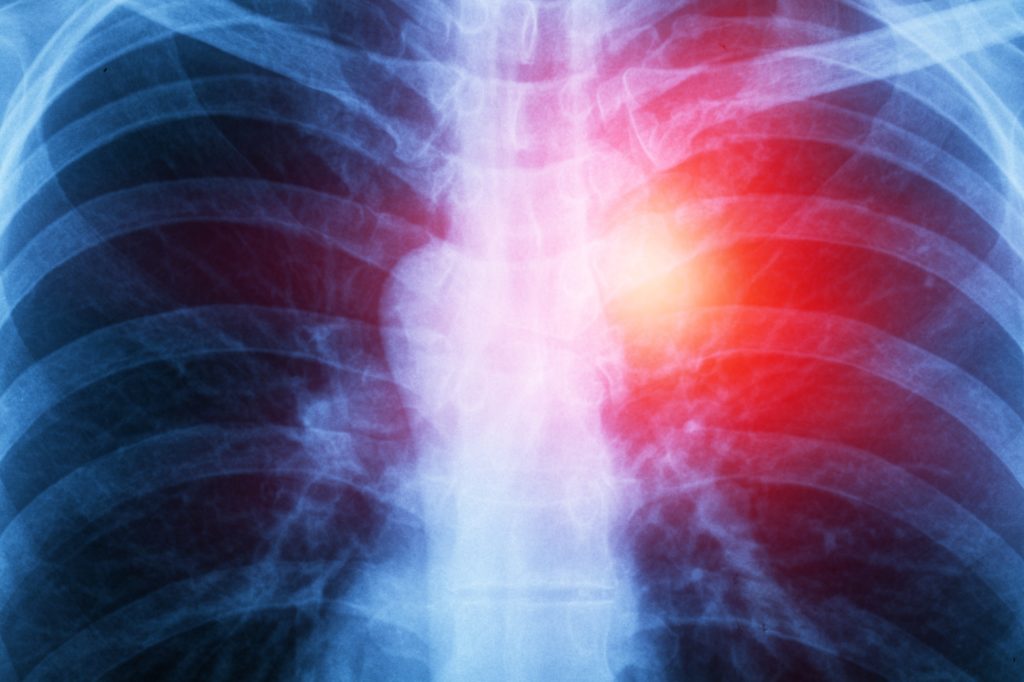

The target of their study was to determine the number of people in Thailand that died with traces of asbestos in their lungs in the period of one year. The analysis they conducted showed that of 200 autopsies the substance was present in nearly half of them (48.5%) with the gender, cause of death and age not even considered with this research. Shockingly there were even traces found in the lungs of a two-year-old who died of congenital heart disease.

After their findings were reported co author of the study, Dr Pimpin Incharoen, shared his surprise at the high level of asbestos found. This number is much higher than in 1985 when a similar study found only 33% of the autopsies had traces, he believes this is a clear indication of the struggle of removing asbestos from the body once it has been inhaled.